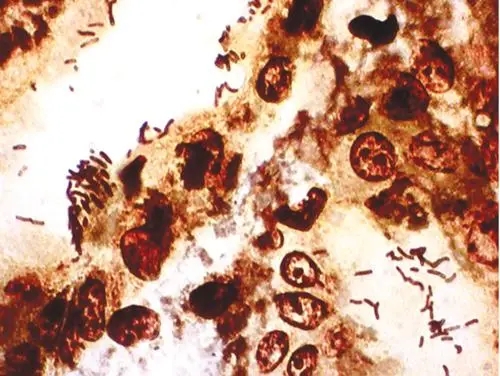

吉姆萨染色:染色原理和结果与瑞特染色法基本相同。但该法对细胞核和寄生虫着色较好,结构显示更清晰,而胞质和中性颗粒则着色较差。为兼顾二者之长,可用复合染色法。即以稀释吉姆萨液代替缓冲液,按瑞特染色法染1

吉姆萨染色:染色原理和结果与瑞特染色法基本相同。但该法对细胞核和寄生虫着色较好,结构显示更清晰,而胞质和中性颗粒则着色较差。为兼顾二者之长,可用复合染色法。即以稀释吉姆萨液代替缓冲液,按瑞特染色法染10min.或先用瑞特染色法染色后,再用稀释吉姆萨复染。